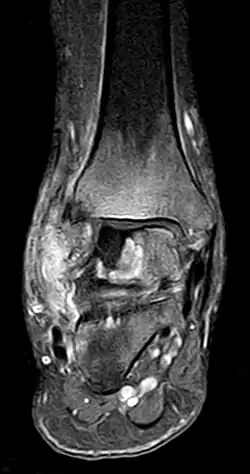

- Stadium ARCO 0

Im Anfangsstadium sind in konventionellen Röntgenaufnahme keine krankhaften Veränderungen zu erkennen. In seltenen Fällen ist eine dezente Auflockerung der Knochenfeinstruktur (Trabekel) in dem betroffenen Areal zu erkennen: das Ausmaß dieser Auflockerung ist jedoch zumeist so gering, dass es nicht sicher erkannt werden kann. In der Kernspintomographie (MRT) ist in diesem Stadium ein Bild analog dem Knochenmarködem (KMÖ, transiente Osteoporose; bone marrow edema, BME) zu erkennen. Unter Verwendung der short tau inversion recovery (STIR) Aufnahmesequenz wird eine Signalhyperintensität (helles Aufleuchten im Graustufen-Kernspinbild) festgestellt (vergleiche Bild 1a und 2 helle Ränder). Eine sichere Unterscheidung zwischen dem prinzipiell reversiblen Bild eines KMÖ/BME und dem Stadium ARCO I einer aseptischen Knochennekrose ist nicht mittels des Kernspintomogramms möglich.

Reversibles Frühstadium (MRT-positiv/reaktive Randzone)

Irreversibles Frühstadium (Röntgen positiv)

_-_MR_Coronal_STIR_-_child_13_yrs_after_ALL_-_01.jpg)